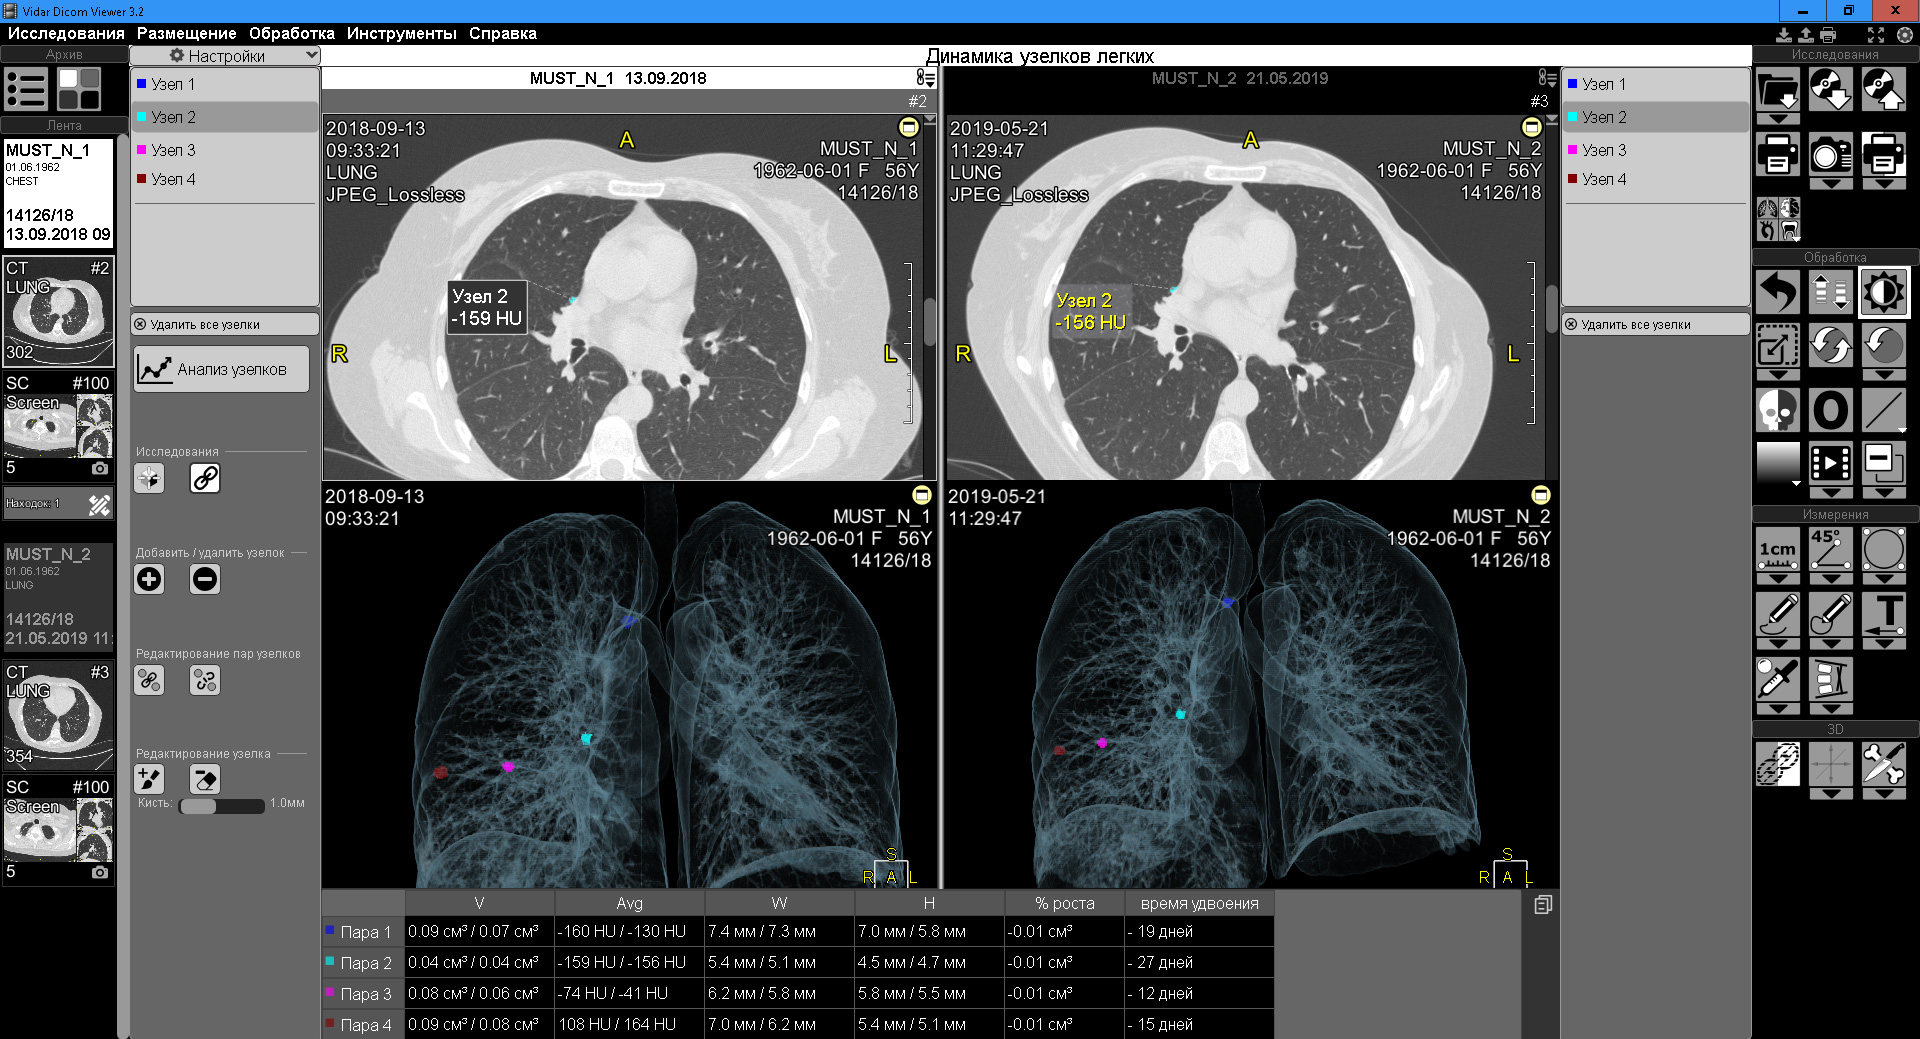

Онлайн DICOM-вьюеры предлагают широкий набор инструментов для анализа изображений. Пользователи могут проводить измерения, такие как размеры опухолей или длина сосудов, а также контурировать области интереса для более детального изучения. Эти функции помогают врачам более точно оценивать состояние пациента и принимать обоснованные решения о лечении.

С облачными DICOM-вьюерами пользователи могут хранить медицинские изображения и связанные с ними данные в безопасном облачном хранилище. Это обеспечивает простоту доступа и защиту информации. Кроме того, возможность делиться изображениями и отчетами с коллегами или пациентами в режиме реального времени значительно упрощает процесс диагностики и лечения.